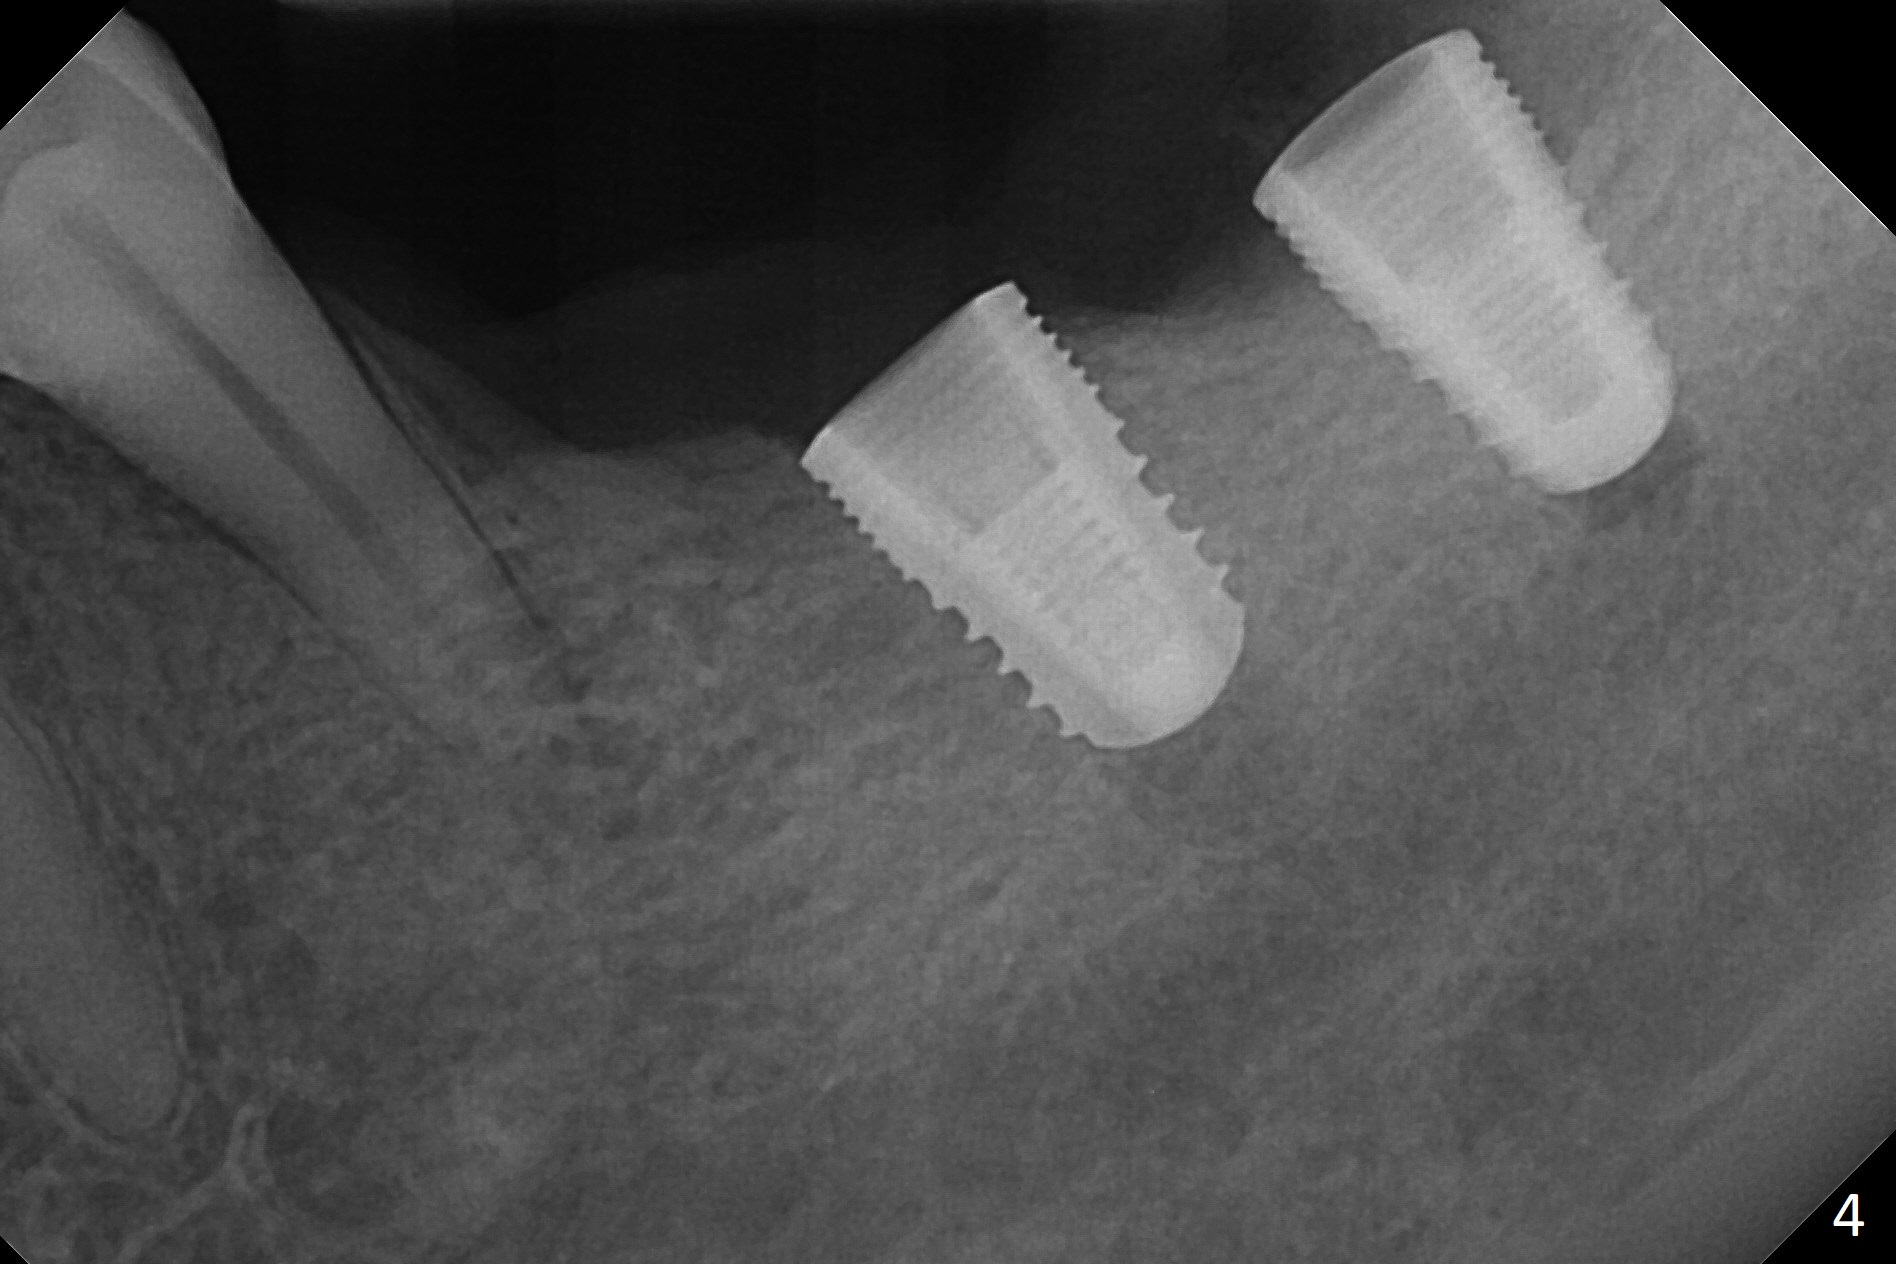

Preop photo shows severe mesial tilt of the tooth #18 (Fig.1). After extraction, the osteotomy is established in the apical end of the socket, where the buccolingual width is limited. It appears that an extra wide implant (5.9 mm) may perforate one of buccolingual plates. On the other hand, the buccal plate (Fig.2 double arrows) is intact and approximately 2 mm tall, whereas the lingual one is thin and lower. Initial osteotomy confirms that bone heights at #18 and 19 are 6 and 8 mm, respectively. Counting 2 mm of the buccal plate and bone graft lingually, a 8 mm long implant may be a practical option at the site of #18. After initial placement of two of 5x8 mm SM implants (Fig.3), the depth of the implant at #19 is adjusted twice (Fig.4,5). With placement of autogenous and allograft (Vanilla, Fig.5 *)) and abutments, a piece of cotton pellet is placed in each abutment well (access, Fig.6 *). Periodontal dressing is applied to the abutment wells for additional retention (Fig.7 *). Due to local poor oral hygiene, splinted provisional is fabricated 4 months postop (Fig.8) in preparation for limited orthodontic uprighting the tooth #20. The patient has pain with mastication at #18 eleven months post cementation (Fig.9). It appears that both of the implants should be removed with immediate replacement and bone graft. Prepare 4 PRF and sticky bone. The new implant will be 5.0 or 5.5x5 mm (Fig.10 green) with 2.3 mm platform (white). A block graft will be harvested from the ipsilateral ramus using 9/8 and 6/5 mm trephine burs for 2-3 mm in depth (Fig.11 blue). The ring graft will be seated around the platform over the implant (Fig.12).